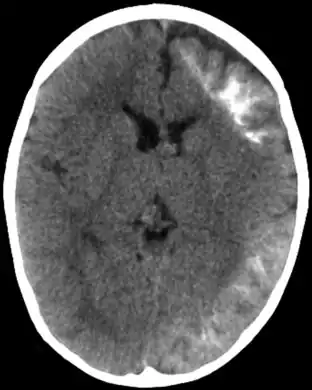

A Síndrome de Sturge-Weber, às vezes chamada angiomatose encefalotrigeminal, é uma doença extremamente rara, congênita, neurológica e também é uma desordem de pele. É uma facomatose, e é freqüentemente associada com glaucomas, manchas de coloração vinhosa, ataques apopléticos, retardamento mental e angioma leptomeningeal ipsilateral. É causada por uma má-formação artério-venosa que acontece num dos hemisférios do cérebro, do mesmo lado dos sinais físicos descritos acima. Normalmente, só um lado da cabeça é afetado.

Também há má formação de vasos sanguíneos na pia-máter do cérebro, do mesmo lado da cabeça que a marca de nascença. Isto causa calcificação do tecido e perda de células do nervo no córtex cerebral.